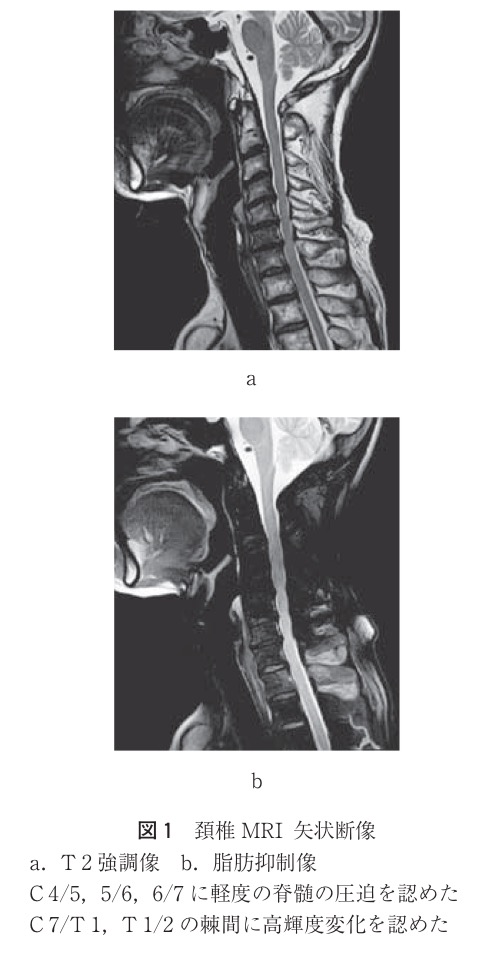

MRI:軽度の脊髄圧迫・狭窄なし、C7~T2で高輝度変化有り